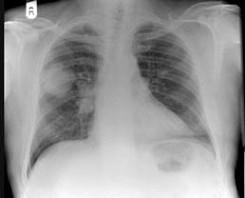

58岁,男,咳嗽、气促3个月,抽烟二十余年,请结合胸片图选择最可能的诊断 ( )A、错构瘤B、结节病C、胸膜间皮瘤D、肺结核E、肺癌